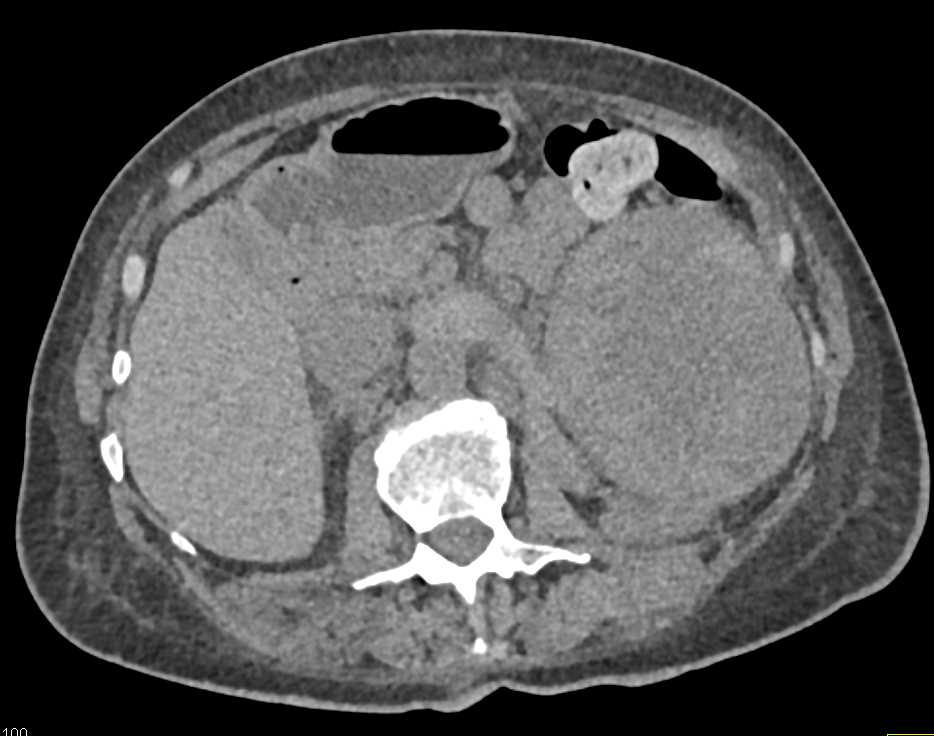

Vasculitis with Thickening of the Superior Mesenteric Artery (SMA)